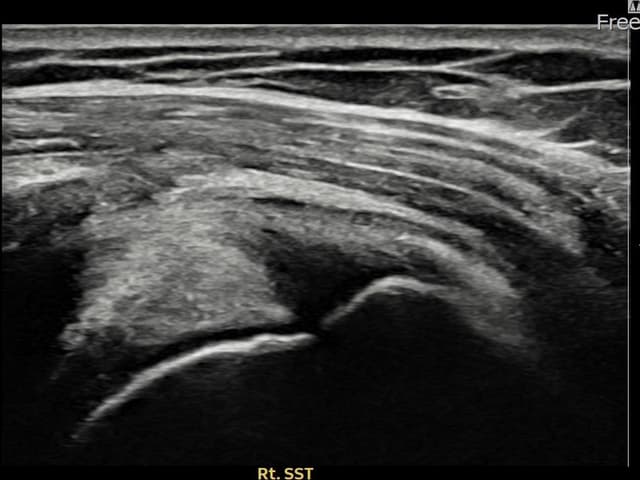

[촬영시기:23.09.01~23.11.03]

[어깨인대 축소봉합술] 우측 어깨 통증이 수개월간 지속되어 내원하셨습니다.